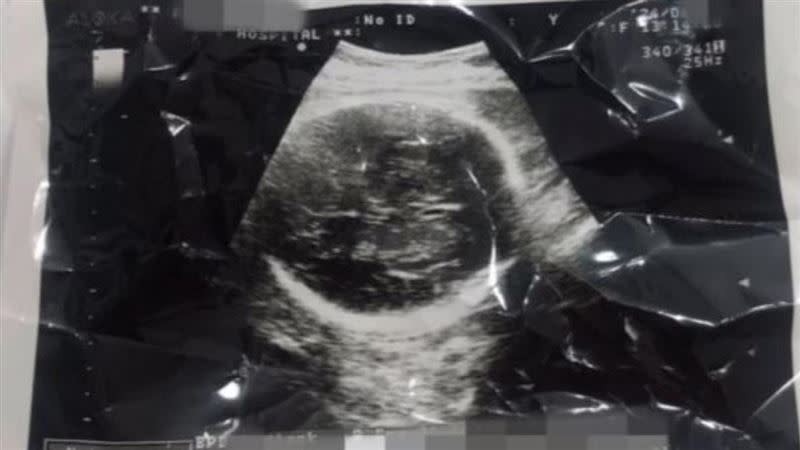

根據檢方調查,權女在2024年6月懷孕達34至36週時,前往該診所進行剖腹產手術。令人心碎的是,胎兒在取出時仍具備呼吸與心跳,屬於「活產」狀態。